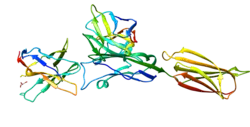

Programmed death-ligand 1 (PD-L1) also known as cluster of differentiation 274 (CD274) or B7 homolog 1 (B7-H1) is a protein that in humans is encoded by the CD274 gene.[5]

Programmed death-ligand 1 (PD-L1) is a 40kDa type 1 transmembrane protein that has been speculated to play a major role in suppressing the adaptive arm of immune systems during particular events such as pregnancy, tissue allografts, autoimmune disease and other disease states such as hepatitis. Normally the adaptive immune system reacts to antigens that are associated with immune system activation by exogenous or endogenous danger signals. In turn, clonal expansion of antigen-specific CD8+ T cells and/or CD4+ helper cells is propagated. The binding of PD-L1 to the inhibitory checkpoint molecule PD-1 transmits an inhibitory signal based on interaction with phosphatases (SHP-1 or SHP-2) via Immunoreceptor Tyrosine-Based Switch Motif (ITSM).[6] This reduces the proliferation of antigen-specific T-cells in lymph nodes, while simultaneously reducing apoptosis in regulatory T cells (anti-inflammatory, suppressive T cells) – further mediated by a lower regulation of the gene Bcl-2. PD-L1 is expressed on both hematopoietic and nonhematopoietic cells in tissues. However, the exact roles of PD-L1 on hematopoietic versus nonhematopoietic cells in modulating immune responses are unclear.[7]

In an ancestor of tetrapod species, PD-L1 and PD-L2 arose from a gene duplication.[8][9][10] Both PD-L1 and PD-L2 can bind PD-1.[11] While across mammals the PD-L1 and PD-L2 molecules also show consistent differences in the membrane-distal IgV domain,[8] across tetrapod species they only show consistent differences in their membrane-proximal IgC domain (see Figure 3).[9]

PD-L1 binds to its receptor, PD-1, found on activated T cells, B cells, and myeloid cells, to modulate activation or inhibition. The affinity between PD-L1 and PD-1, as defined by the dissociation constant Kd, is 770 nM. PD-L1 also has an appreciable affinity for the costimulatory molecule CD80 (B7-1), but not CD86 (B7-2).[15] CD80's affinity for PD-L1, 1.4 μM, is intermediate between its affinity for CD28 and CTLA-4 (4.0 μM and 400 nM, respectively). The related molecule PD-L2 has no such affinity for CD80 or CD86, but shares PD-1 as a receptor (with a stronger Kd of 140 nM). Said et al. showed that PD-1, up-regulated on activated CD4 T-cells, can bind to PD-L1 expressed on monocytes and induces IL-10 production by the latter.[16]